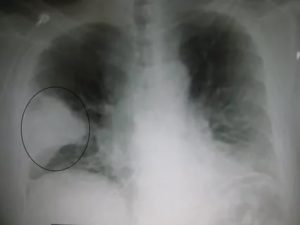

- Абсцедирующая пневмония. Проявляется обширным затемнением пораженной области, признаками утолщения плевры и наличием полостей разного размера, наполненных жидкостью.

Данной форме характерно формирование больших участков поражения легочной ткани. Патологический процесс может охватывать как одно, так и оба легких. На иллюстрации ниже показана тяжелая форма крупозной пневмонии.

Рентген-снимки при крупозной пневмонии характеризуются следующими синдромами:

- Обширное (тотальное) снижение прозрачности легочной ткани.

- Субтотальное затемнение – при локализации воспаления в пределах одной или двух долей легких.

- Ограниченное затемнение – инфильтративные изменения легочной ткани, не выходящие за пределы сегмента.

При слиянии отдельных очагов воспаления легочной ткани возникает крупозная пневмония. Фото рентгеновского снимка, сделанного при этой форме заболевания, наглядно показывает отличия.

Как правило, при крупозной форме воспаления легких поражается одна или несколько долей легких сразу. Это создает серьезную угрозу жизни пациента.

На рентгене крупозная форма болезни проявляется следующими признаками:

- Ярко выраженные крупные тени, затрагивающие доли легкого целиком. Могут быть поражены оба легкого.

- Средостение смещается в сторону наиболее воспаленного легкого.

- На куполах диафрагмы отчетливо видны признаки деформации.

- Рисунок легочной ткани может не просматриваться.

Крупозная пневмония легче всего выявляется при рентгенологическом исследовании. Тем не менее для постановки точного диагноза врачи предпочитают делать рентгеновские снимки в двух проекциях. Это дает им возможность определить число пораженных воспалением сегментов органа и определить состояние средостения.